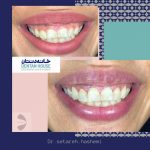

دکتر ستاره هاشمی در تهران

دکتر ستاره هاشمی در تهران

جراح و متخصص بیماری های لثه و ایمپلنت

جراحی های افزایش طول تاج در نواحی زیبایی